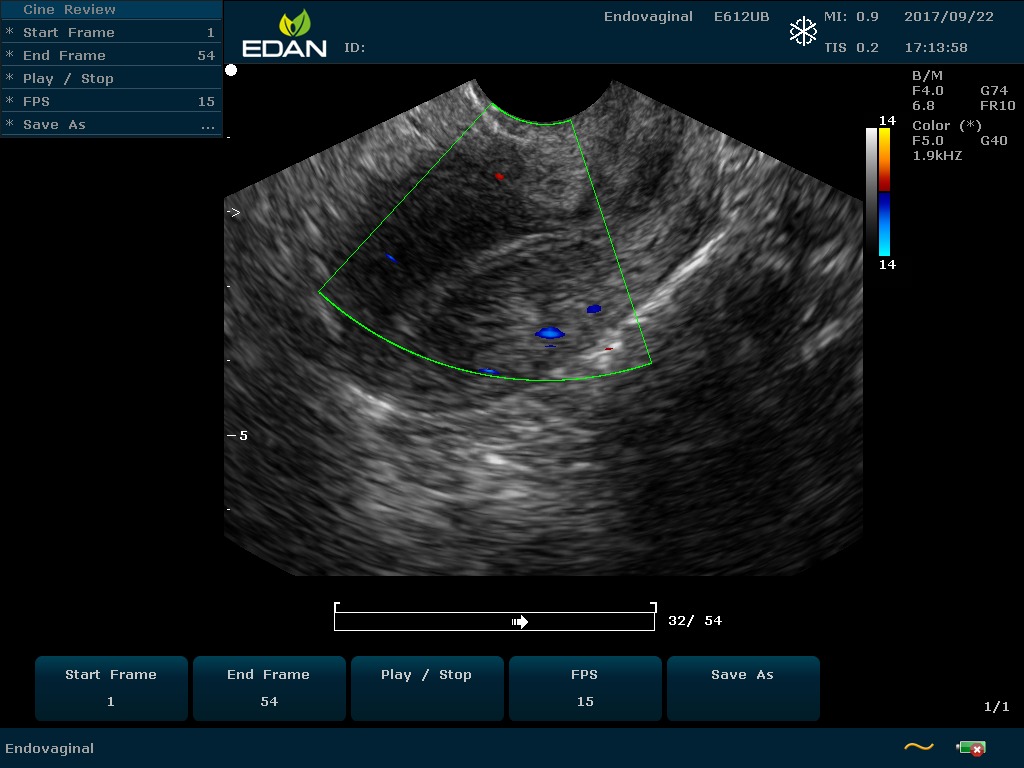

Особенность U60 Edan — расширенное применение. Ультразвуковой аппарат рекомендован для абдоминальных исследований, гинекологии и акушерства, кардиологии, педиатрии, урологии, изучения малых органов, сосудов. Для U60 Edan используются конвексные, линейные, фазированные и внутриполостные датчики.

Передовые технологии позволяют повысить качество визуализации в несколько раз. УЗИ-аппарат U60 Edan отличается возможностью быстрой настройки визуализации. Специальные функции позволяют моментально отображать данные за счет быстрой оптимизации параметров. Режимы визуализации: B-mode, M-mode, Color Doppler, Power Doppler Imaging, Pulsed Wave Doppler, Continuous Doppler.

• Цветовое Допплеровское картирование

• Направленная энергетическая Допплерография